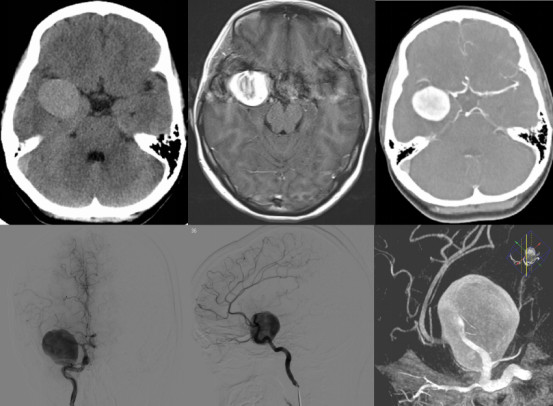

手术经过:患者全麻后取仰卧位,头左转约30°左右,略后仰,颧弓位于高点,三点头架固定,抬高背板20°左右,右侧翼点入路标记。术区常规消毒铺巾,切开额颞头皮,牵开固定。磨钻,铣刀形成额骨瓣8*6cm左右,脑膜四周悬吊弧形剪开。显微镜下剪开侧裂中部蛛网膜,释放脑脊液降低颅压,拉抬起额叶,暴露右侧中动脉近端,见动脉瘤位于中动脉M1主干,大小约3.5*4cm,远端可见动脉流出道。用临时瘤夹夹闭中动脉近端,使动脉瘤张力下降,仔细分离动脉瘤与周围小血管粘连,用探针分离动脉瘤两缘,再用一枚临时瘤夹夹闭中动脉远端流出道分支动脉,用尖刀片刺破动脉瘤,吸除瘤内积血后动脉瘤体积进一步缩小。小心分离瘤颈,暴露清晰后,取动脉瘤夹4枚并排塑形并夹闭动脉瘤。放开临时瘤夹后未见明显出血,术中荧光造影见中动脉远端通畅,冲洗术野未见明显出血,修补缝合硬脑膜,回纳骨瓣,缝合颞肌头皮后术毕。

该病人术中荧光造影显示动脉瘤近端流入和远端流出均通畅(图3),但术后出现左侧不全偏瘫,头颅MRI+DWI提示右侧额颞岛叶皮层及基底节区梗死灶。我们考虑这与术中由于瘤体巨大而不可避免的血管牵拉,以及蛛网膜下腔出血导致的一过性脑血管痉挛相关,经抗血管痉挛治疗后患者左侧肢体肌力恢复至正常,这也更加证实了我们的判断。通过这样的病例可见,动脉瘤性蛛网膜下腔出血的患者术后应严格控制血压,预防低灌注的发生,而抗血管痉挛可以有效改善动脉瘤性蛛网膜下腔出血后脑血管痉挛导致的临床症状。

图3. 术中荧光造影:提示动脉瘤近端流入及远端流出均通畅。